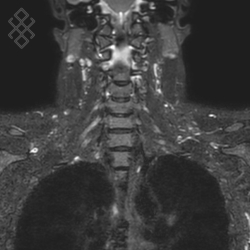

IRM du Rachis cervical

Vous entrez dans l'aimant, ouvert des 2 côtés, la tête la première et allongé sur le dos. Ensuite, pour recueillir le signal et construire les images, vous aurez la tête dans une antenne. Étant donné que cet examen est très bruyant, vous aurez à votre disposition des tampons auriculaires pour atténuer le bruit de la machine.

La durée moyenne de l'examen est de 25 min. Dans le cas d'une injection, le manipulateur en radiologie vous administrera le produit de contraste. Vous entendrez un bruit caractéristique à l'IRM faisant penser à un marteau piqueur.